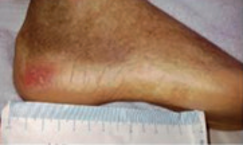

Suspected deep tissue injury (SDTI)

An SDTI may appear as a bruise or present as a blood-filled blister over a wound bed. This may be less obvious in a dark skin tone.

Area may be painful, changes in temperatures and texture may be present.

Some SDTI pressure ulcers resolve or stay static. Sometimes skin will degrade and develop into deeper tissue loss.

Once grade can be established, this must be documented.

Suspected deep tissue injurySuspected deep tissue injurySuspected deep tissue injury